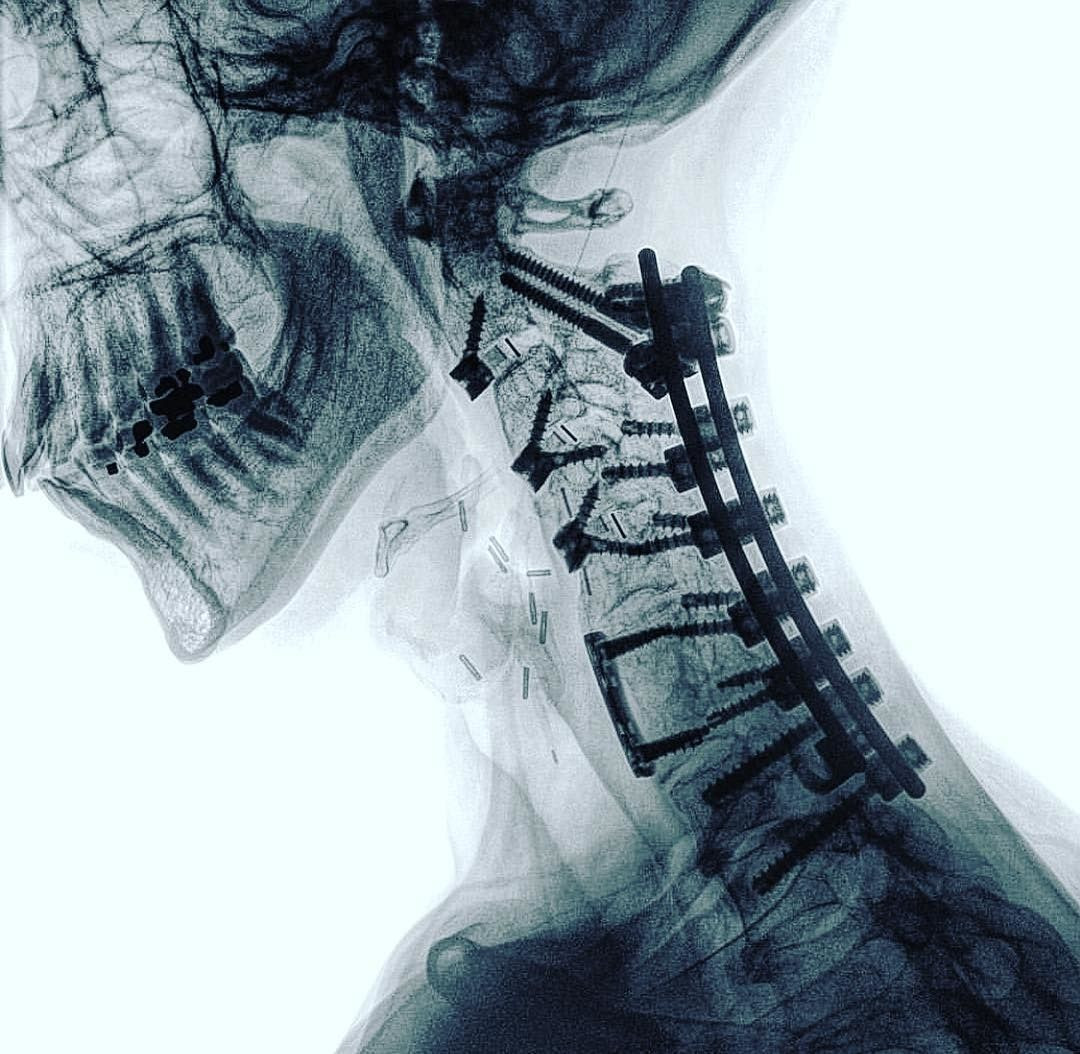

Nhờ các thực nghiệm, ông biết rằng tia X xuyên qua da thịt người nhưng không để xuyên qua những chất có mật độ cao như xương hoặc chì, và chúng có thể được chụp ảnh lại.

Phát hiện của Rontgen được xem là một phép màu y học thời đó, và tia X sớm trở thành một công cụ chẩn đoán quan trọng trong y học, cho phép các bác sĩ nhìn thấy bên trong cơ thể người mà không cần phẫu thuật.